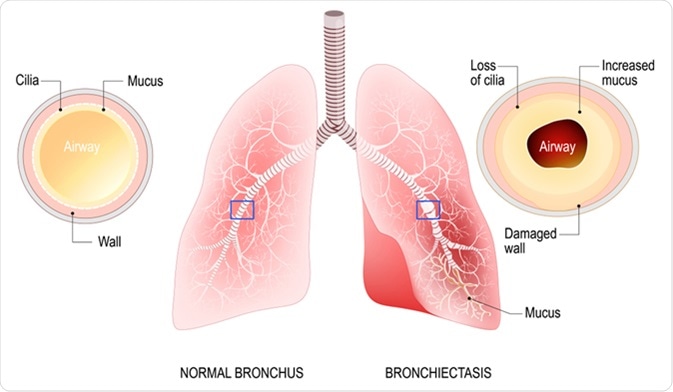

Bronchiectasis is a chronic condition of the respiratory system, in which there is abnormal widening of the airways due to an initial damaging factor. This in turn reduces the ability of the bronchi to clear mucosal secretions, thereby leading to an abnormal buildup of mucus. This leads to an increased susceptibility to infections and inflammation that further damage the airways.

Bronchiectasis. Normal bronchus and bronchiectasis. Enlarged small airways that collect mucus and cause recurrent lung infections. Image Credit: Designua / Shutterstock